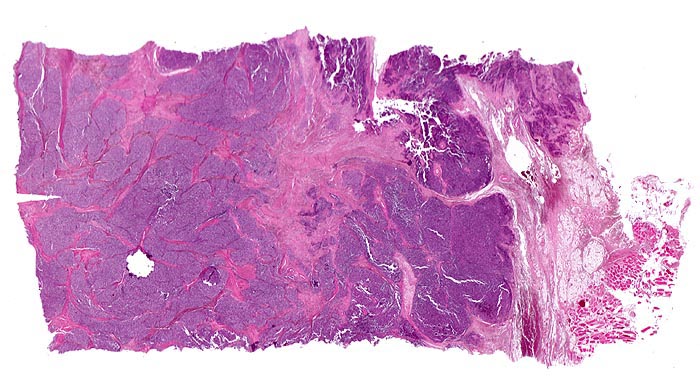

Morphologische Merkmale:

• Durch Bindegewebssepten abgegrenzte Knoten (lobuläre Architektur).

• Blauer, klein- und rundzelliger Tumor.

• Uniforme Zellen mit schmalem, kaum abgrenzbarem Zytoplasmasaum und unscharfen Zellgrenzen. Rundliche oder ovale Zellkerne mit leicht vergröbertem Chromatin und punktförmigen kleinen Nukleolen.

• Quetschartefakte (gequetschte Zellen sind dunkler und haben verkleinerte abgeflachte Zellkerne).